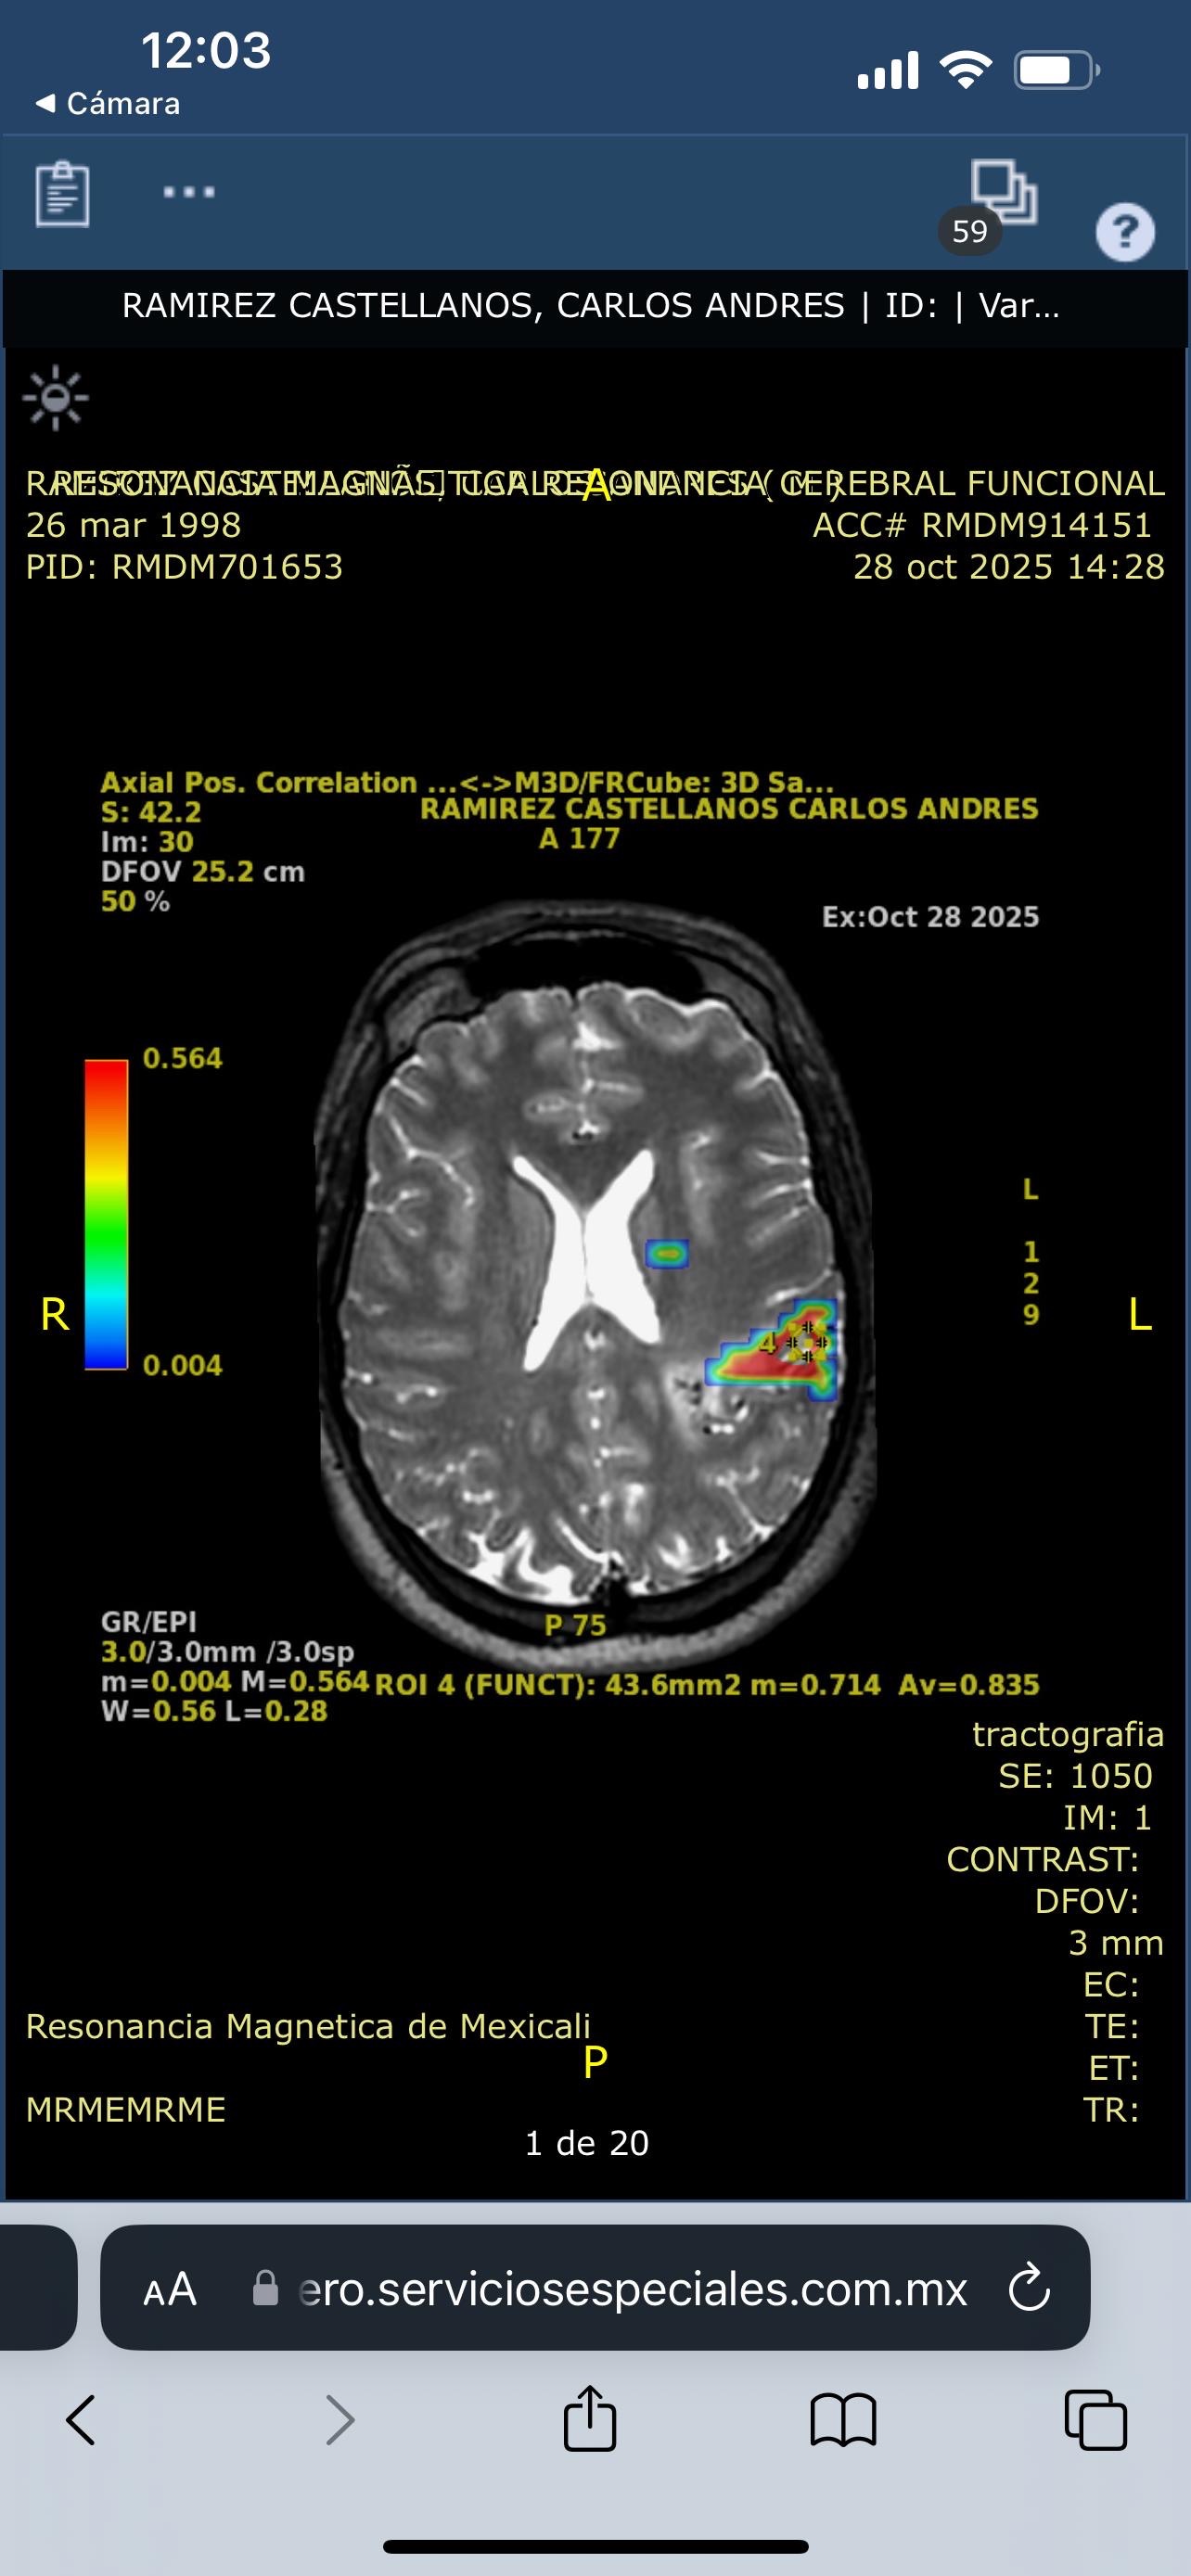

Hoy, lamentablemente, Carlos enfrenta una de las pruebas más difíciles de su vida. Fue diagnosticado con una hemorragia cerebral, una condición grave que avanza rápidamente y requiere una cirugía urgente para salvar su vida.

Today, Carlos is facing one of the toughest battles of his life. He was recently diagnosed with a brain hemorrhage, a serious and rapidly progressing condition that requires urgent surgery to save his life.